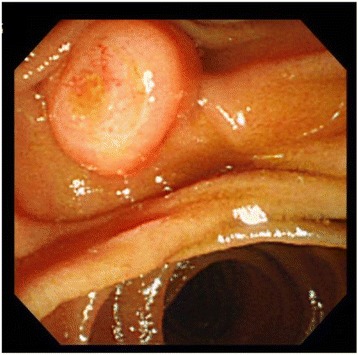

Esophagogastroduodenoscopy (EGD) revealed mildly swollen papilla of Vater, without any mucosal erosion (Fig. 1).